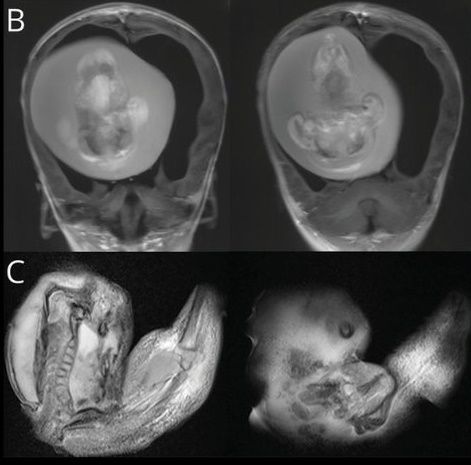

10일 홍콩01 등 현지 언론에 따르면 지난해 12월 신경학 저널에 중국 푸단 대학 병원 의사들이 1세 여아 두개골 안에서 일란성 쌍둥이 기생 태아를 제거했다는 사례가 보고됐다.

당초 아이는 대두증과 운동 능력 상실을 이유로 부모와 함께 병원을 방문했다. 의료진은 아이 머리에 단순 종양이 있다고 판단해 CT(컴퓨터 단층 촬영)를 찍었다. 하지만 의료진 예상과 정반대의 결과가 나왔다. 아이 두개골에서 태아가 발견된 것이다.

두개골 속 태아는 웅크린 채 뇌를 짓누르고 있었다. 아이와 연결된 혈관으로부터 양분을 공급받아 뼈와 팔, 손까지 발달한 상태였다. 아이는 두개골에 자리를 차지하고 있는 태아로 인해 뇌 일부분에 척수액이 고이는 수두증(물뇌증)을 앓고 있었다.

의료진은 즉시 기생 태아를 두개골에서 제거했다. DNA 분석 결과 해당 태아는 아이의 쌍둥이였던 것으로 조사됐다. 도태돼야 하는 분리된 수정란이 전뇌로 발달하면서 이 같은 사례가 발생한 것이다.